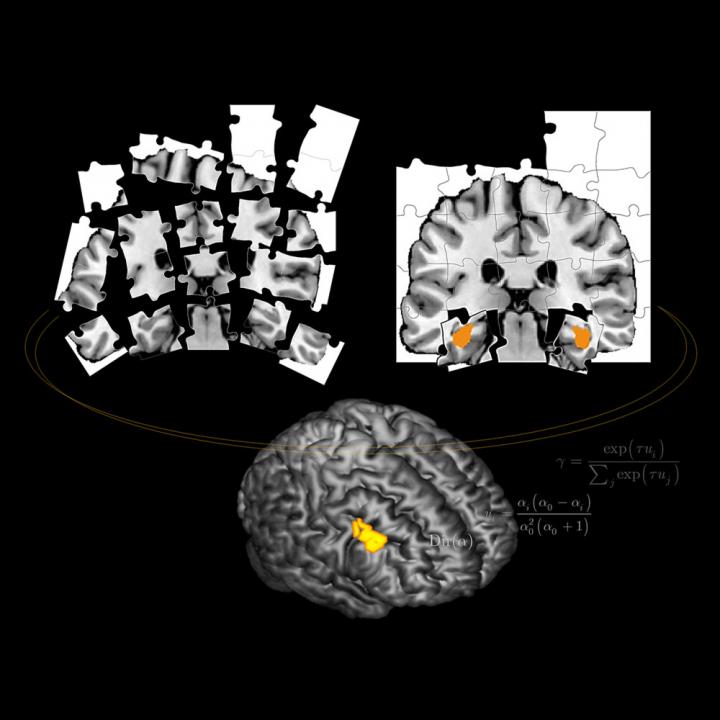

The researchers have also identified a part of the prefrontal cortex--the large brain area located immediately behind the forehead that is associated with complex cognitive activities--that appears to evaluate such causal uncertainty and then activate one-shot learning when needed.

The researchers used a simple behavioral task paired with brain imaging to determine where in the brain this causal processing takes place. Based on the results, it appears that the ventrolateral prefrontal cortex (VLPFC) is involved in the processing and then couples with the hippocampus to switch on one-shot learning, as needed.

Indeed, a switch is an appropriate metaphor, says Shinsuke Shimojo, Caltech's Gertrude Baltimore Professor of Experimental Psychology. Since the hippocampus is known to be involved in so-called episodic memory, in which the brain quickly links a particular context with an event, the researchers hypothesized that this brain region might play a role in one-shot learning. But they were surprised to find that the coupling between the VLPFC and the hippocampus was either all or nothing. "Like a light switch, one-shot learning is either on, or it's off," says Shimojo.

Still, the researchers are intrigued by the fact that the VLPFC is very close to another part of the ventrolateral prefrontal cortex that they previously found to be involved in helping the brain to switch between two other forms of learning--habitual and goal-directed learning, which involve routine behavior and more carefully considered actions, respectively. "Now we might cautiously speculate that a significant general function of the ventrolateral prefrontal cortex is to act as a leader, telling other parts of the brain involved in different types of behavioral functions when they should get involved and when they should not get involved in controlling our behavior," says coauthor John O'Doherty, professor of psychology and director of the Caltech Brain Imaging Center.